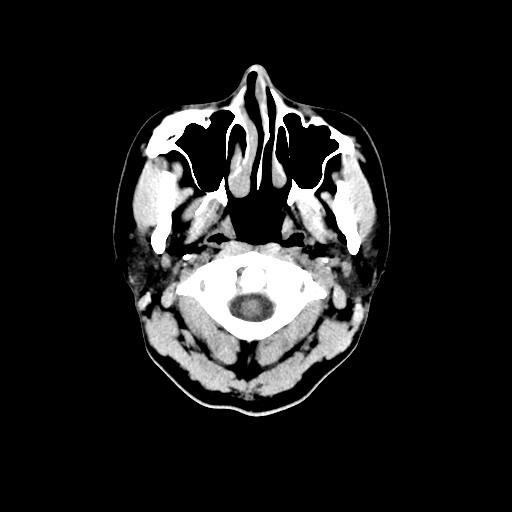

CT検査は様々な方向からX線を当て体内の水分や骨、空気など成分の違いを区別して画像を生成することで、レントゲン等では得ることができない臓器の状態を詳細に把握することが可能となり、小さい腫瘍などをより明確に映し出すことができます。

また、多角的に体内の断面図を得ることができるため立体的に構造を理解することが可能になり、病変の位置や広がりをより詳細に判断することが可能になります。

CT装置は列数が多くなると一度に広範囲の撮影が可能となり、息止め時間が短くなるため少ない負担で検査を受けて頂けます。また、より細かい断層(輪切り)画像を撮る事ができ、病変の抽出能が上がることは早期発見に繋がります。